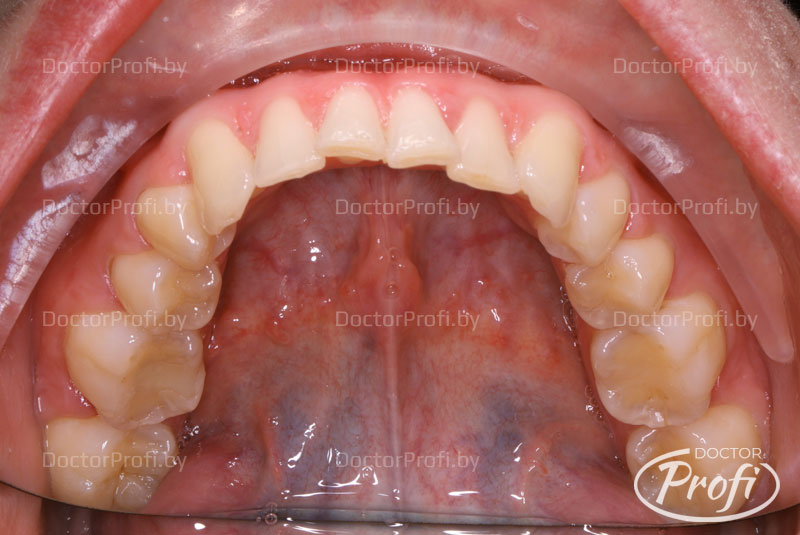

Исправление глубокого дистального прикуса брекет-системой Damon

Пациентка обратилась в клинику с жалобами на неэстетичный зубной ряд. Возраст - 29 год. На консультации у ортодонта были выявлены следующие проблемы с прикусом: дистальный прикус, глубокое перцовое перекрытие, сужение и укорочение зубных рядов, повороты зубов, скученность.

До